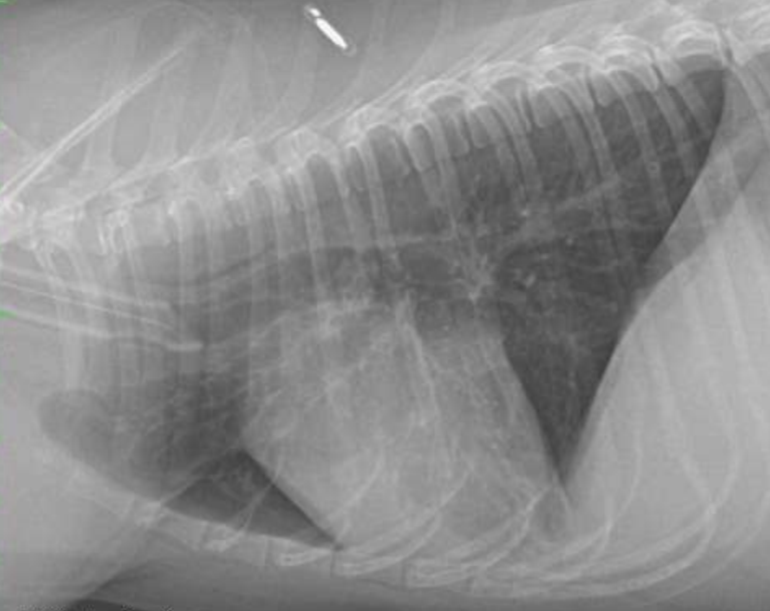

• what lung pattern is seen below?

bronchial

• what pattern is seen below?